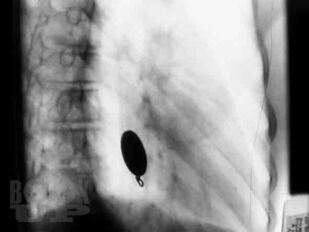

Сборник включает вызвавшие наибольший интерес аудитории лекции и доклады на различных научно-практических конференциях в 2017–2018 гг. по актуальным проблемам пульмонологии и аллергологии детского возраста, таким как: современные методы диагностики и лечения, острые и хронические инфекционно-воспалительные и аллергические заболевания органов дыхания, муковисцидоз, туберкулез органов дыхания, а также обмен опытом, интересные случаи из медицинской практики, различные другие информационные материалы. Ежегодник адресован практикующим детским пульмонологам и аллергологам.